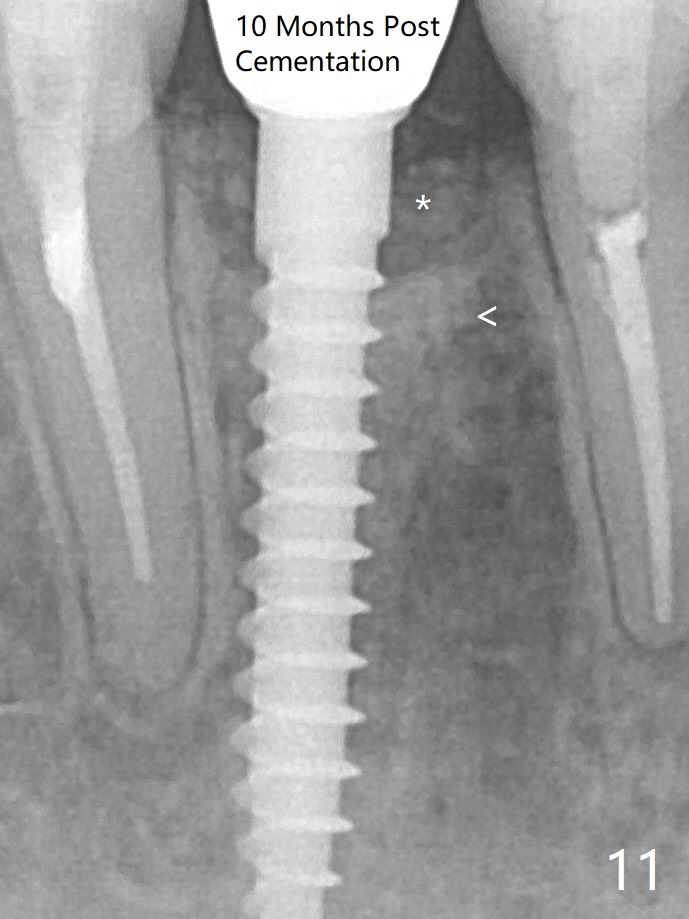

A drawback of implant planning at #25 is not to use a preop PA (Fig.1 (^ fracture line)). The initial trajectory seems to be alright (Fig.2 (red line: socket; D: 1.2 mm drill)), but a 2.5x14(2) mm implant placed is close to the tooth #26 (Fig.3 (allograft having been placed)). The latter may be related to more bone loss in the distal crest 3.5 months postop (Fig.8) and more severe distal papillary recession (Fig.9 *). The meisal bone seems to be wider. The bone density increases at the levels of the non-thread and thread portions of the implant (in the original socket) nearly 10 months post cementation (Fig.11 *, <). The bone density increase is related to deep placement of the implant.